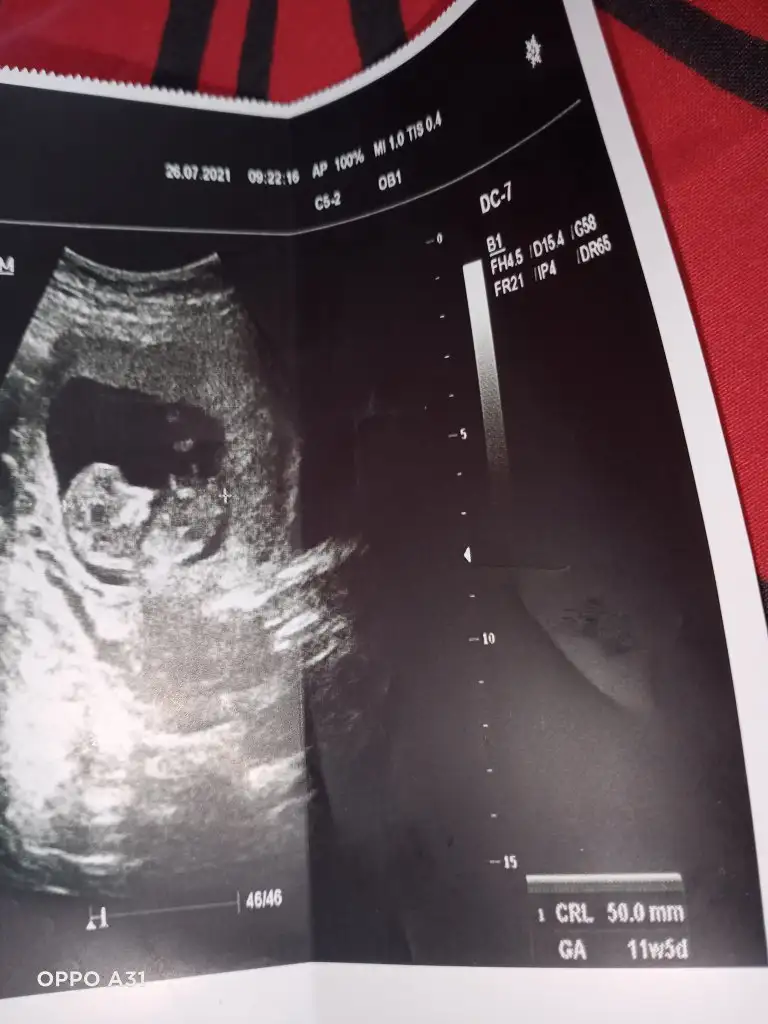

Kız gibi sanki emin olamadımEki Görüntüle 2892053 Eki Görüntüle 2892054 @Ikra meyra acaba müsait olunca bakar mısın? 11+6 oldu belli olur mu biraz?

Teşekkür ederimKız gibi sanki emin olamadım

Bugün cinsiyetini öğrendik,kızımız olacak. Teşekkürler zaman ayırdığınız için.Erkek gibi sanki

Benim bebeğime de bakar mısınız 9 buçuk haftalık. Belki erken ama bir yorumunuz olursa diye merak ediyorumEn iyi 11 12 13 haftalar olmalışimdilik erkek yönünde ama yanıltabilir dediğim haftalar olmalı

Erkek görünüyor

Şimdilik erkek yönünde ama en iyi 11 12 13 haftalar olmalı tekrar USG paylasinBenim bebeğime de bakar mısınız 9 buçuk haftalık. Belki erken ama bir yorumunuz olursa diye merak ediyorum